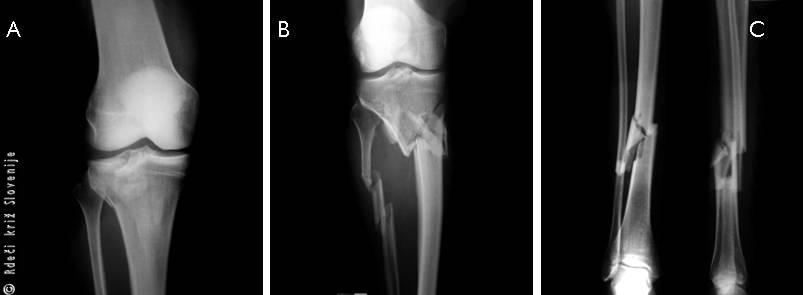

Slika 3

A – Zaprt zlom goleni.

B – Zaprt zlom in izpah gležnja. Kostni odlomek pritiska na kožo od znotraj brez rane.

C – Odprt zlom goleni s poškodbo mehkih tkiv.

D – Odprt zlom goleni s prekinjeno prekrvitvijo poškodovanega uda pod zlomom.

Oceno o zaprtem oz. odprtem zlomu lahko postavimo že na mestu poškodbe, ob nudenju prve pomoči, za ostale natančne razdelitve zlomov pa je potrebno rentgensko ali globinsko slikanje in skeniranje in sodi v bolnišnico.